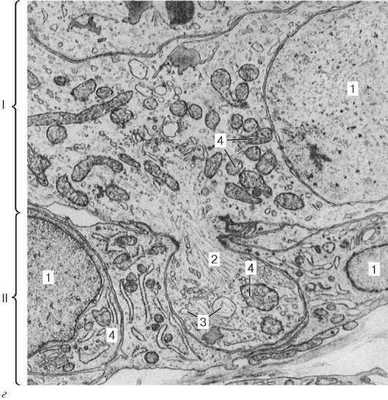

Рис. 15.7. Эпифиз:

а - общий вид эпифиза человека (схема); б - микрофотография паренхимы эпифиза ребенка 1 года 2 мес (по Л. И. Салийчук); в - микрофотография эпифиза человека 63 лет (по Л. И. Салийчук): 1 - соединительнотканная капсула; 2 - соединительнотканная перегородка; 3 - паренхима эпифиза; 4 - мозговой «песок»; 5 - кровеносные сосуды; 6 - глиоциты; 7 - темные пинеалоциты; 8 - светлые пинеалоциты

Рис. 15.7. Продолжение

г - эпифиз крысы. Электронная микрофотография, увеличение 12 000 (по Г. А. Косолапову): I - светлый секретирующий пинеалоцит; II - глиоцит; 1 - ядро; 2 - булавовидный отросток; 3 - вакуоли; 4 - митохондрии